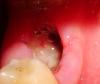

Danija Опубликовано 7 июля, 2010 Поделиться Опубликовано 7 июля, 2010 Добрый день.Два года назад констатировали кисту около зуба( появиласьиз-за недоконца заделанного канала), так как зуб перестал болеть врач сказала что можно не удалять( у того врача больше не обследуюсь).Сейчас спустя два года, начала болеть десна и появляться опухоль на десне, всё сильней и сильней, и лимфоузлы тоже начали болеть и ещё до кучи соседние зубы.Поехала к клинику, зуб удалили, по незнанию в первый день полоскала рот, и скорее всего нужный сгусток ушел....Лимфоузлы не болят, соседный зуб не болит, припухлость десны медленно и уменьшается.Единственное, что волнует это то что десна чуть чуть ноет, то чешется изнутри и касание десны со стороны щеки вызывает боль.Когда не кушаю, ничего не волнует. Но не кушать не получается Полоскать чем то уже боюсь, мало ли хуже станет.Прочитала в нете , что если удалить нужный сгусток, то непременно начнеться альвеолит.К врачу есть возмоность попасть только в следующию среду.Фото прилагается.Заранее спасибо Ссылка на комментарий